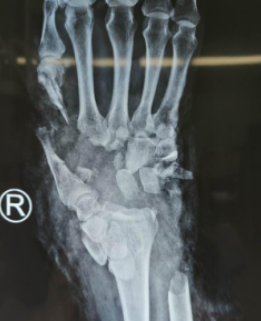

下午4点钟,吴尧、王江鹏医疗小组为患者完善各项术前检查后,进入手术室开始手术。张大爷不是简单的离断伤,他的骨头碎裂、缺损,手术难度非常大。术中见其右腕关节自桡骨远端以远斜行不全离断,仅掌桡侧部分皮肤软组织相连,离创缘不齐,创面挫伤污染严重,内见大量油污,右手掌侧及背侧见多处皮肤软组织撕脱伴缺损创面,右尺骨远端1/3骨质缺损。吴尧、王江鹏医疗小组先清除污染失活组织,再把断裂的血管、神经、肌腱等一一接上,直到通血成功。由于患者失血过多,术中为其输血,输血过程顺利。手术共进行了8个小时,到深夜12点才结束。无论对医生,还是患者来说,这次手术的考验都是巨大的。